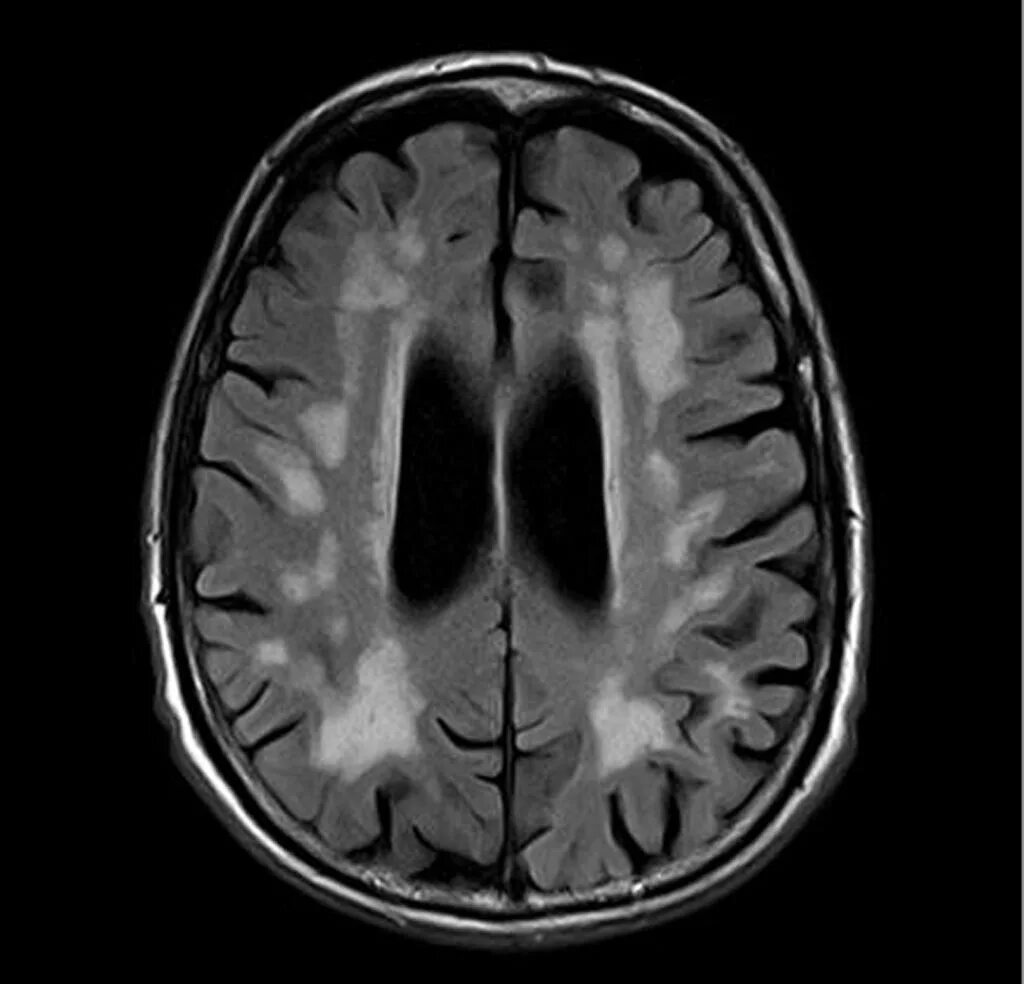

Мрт симптомы